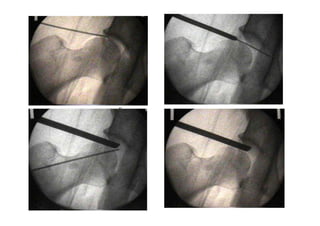

• Módulo 17 - Quadril